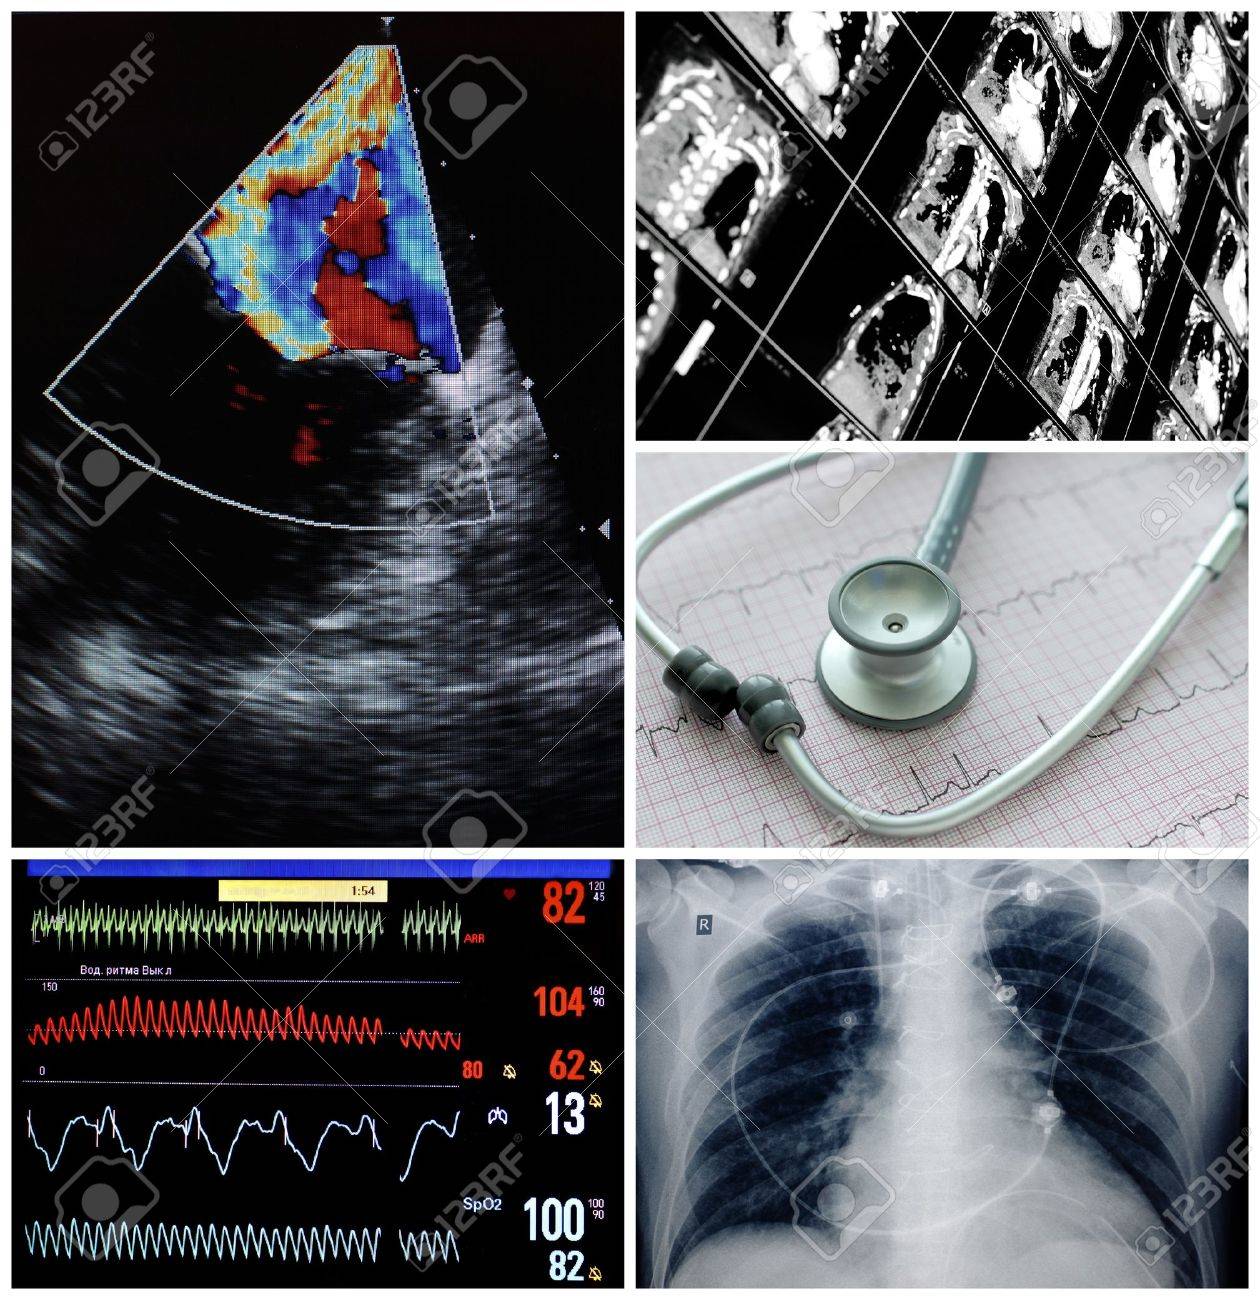

Pruebas de imagen

Utilizan tecnología para obtener imágenes del interior del cuerpo, permitiendo visualizar estructuras y detectar anomalías.

Ejemplos:

- Radiografías

- Ultrasonido

- Tomografía computarizada

- Resonancia magnética.